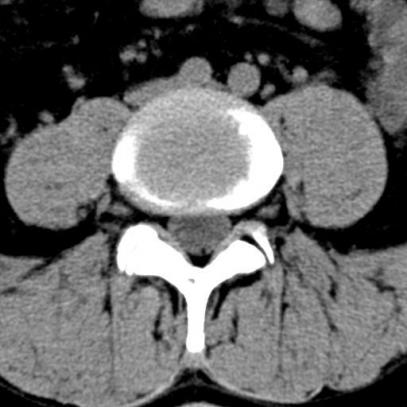

Lumbal spine

Similar to the cervical spine it is enough to initiate an X- ray or a nuclear resonance imaging. If the patient suffers from slipped vertebral bodies or a multiple stenosis it is most helpful to perform a myelographic imaging to get the best impression.